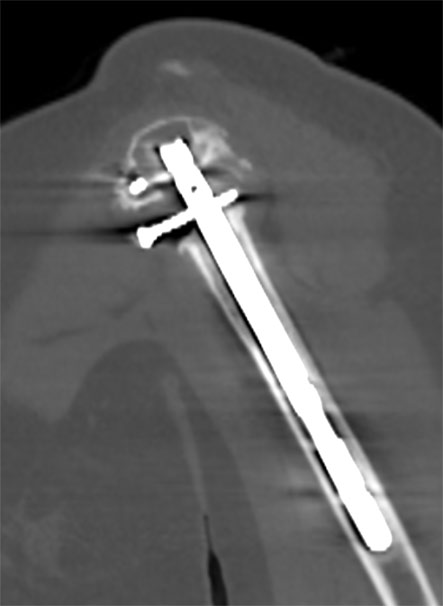

În cazuri speciale, cum sunt prezența de materialele metalice (tije, șuruburi, proteze), ele vor artefacta imaginea puternic, și de aceea atât protocolul de achiziție, cât și cel de postprocesare sunt puțin diferite. Pentru achiziție se vor utiliza parametri electrici cu valori mai mari și slice foarte fin combinat cu un pitch subunitar, eventual cu modificări ale hărții de afișare a nuanțelor de gri (extended CT scale). Din punct de vedere al postprocesării, reconstrucțiile volumetrice cu evidențierea metalului prin transparența osului sunt foarte utile și ușor de înțeles atât de radiolog cât și de ortoped.

Image

Radiografie humerus – material metalic de osteosinteză (tijă)

Computer tomografie humerus cu prezența tijei care artefactează imaginea